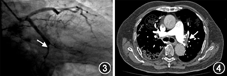

病例1 患者男,63岁,因"胸痛2 h",于2018年1月19日入院。既往无特殊病史。入院体格检查:血压143/70 mmHg(1 mmHg=0.133 kPa),呼吸24次/min,神志清楚;口唇无紫绀,颈静脉无怒张;肺部未闻及啰音;心率60次/min,心律整齐,各瓣膜听诊区未闻及杂音;腹部平软;下肢无水肿。心电图示下壁急性ST段抬高型心肌梗死。心肌肌钙蛋白I 12.000 μg/L,D-二聚体0.32 mg/L,纤维蛋白原3.26 g/L,N末端B型利钠肽原<70 ng/L。冠状动脉造影示:左前降支近段狭窄90%,血流分级为心肌梗死溶栓试验(thrombolysis in myocardial infarction,TIMI)3级;右冠状动脉第一转折处完全闭塞,血流分级为TIMI 0级(图1)。在右冠状动脉闭塞处行血栓抽吸,并置入药物洗脱支架1枚。术前予负荷剂量抗血小板治疗(替格瑞洛180 mg、阿司匹林300 mg),术中静脉推注普通肝素6 000 U,血栓抽吸过程中冠状动脉内先后分次推入替罗非班25 ml,术后常规冠心病二级预防(阿司匹林100 mg,氯吡格雷75 mg,阿托伐他汀20 mg,均每天1次)。患者入院当天大便常规潜血试验(+),考虑合并消化道出血,未使用低分子量肝素。术后患者胸痛症状缓解。次日超声心动图检查示各腔室内径及室壁运动基本正常,左心室射血分数为59%。术后第5天患者突感气短、乏力。心肌肌钙蛋白I为0.310 μg/L,D-二聚体为4.57 mg/L,纤维蛋白原为4.59 g/L。复查心电图未见明显动态变化。下肢血管彩超示双下肢动脉粥样硬化和多发斑块形成,左侧大隐静脉曲张。肺动脉CT血管成像检查示肺动脉主干直径为24 mm,右下肺动脉部分分支充盈缺损(图2),右心径线基本正常,考虑急性肺栓塞。立即皮下注射低分子量肝素4 000 U,每天2次。次日复查凝血功能示D-二聚体为2.86mg/L,纤维蛋白原为3.72 g/L。连续抗凝治疗7 d后,患者症状好转,复查D-二聚体为0.75 mg/L,纤维蛋白原为3.98 g/L,予出院。出院3个月后,复查肺动脉CT血管成像检查示血栓完全消散。

病例2患者男,72岁,因"突发胸痛6 h",于2016年12月29日入院。既往有持续性心房颤动和消化道出血病史。入院体格检查:血压120/80 mmHg,呼吸22次/min,神志清楚;口唇无紫绀,颈静脉无怒张;双侧肺底可闻及少许湿性啰音;心率70次/min,心律绝对不齐,心音强弱不等,各瓣膜听诊区未闻及杂音;腹部平软;下肢无水肿。心电图示下壁和正后壁急性ST段抬高型心肌梗死,心房颤动。心肌肌钙蛋白I为22.000 μg/L,D-二聚体为0.68 mg/L,纤维蛋白原为2.78 g/L,N末端B型利钠肽原为1 880 ng/L。冠状动脉造影检查示左回旋支远端自第二钝缘支发出后完全闭塞,血流分级为TIMI 0级(图3)。行血栓抽吸后,置入药物洗脱支架1枚。术前予负荷剂量双联抗血小板药物治疗(氯吡格雷600 mg、阿司匹林300 mg),造影前静脉推注普通肝素5 000 U,术中经血栓抽吸导管冠状动脉内推注替罗非班20 ml,术后常规冠心病二级预防(氯吡格雷75 mg、瑞托伐他汀20 mg,均每天1次)。患者入院当日大便常规潜血试验(+),考虑合并消化道出血,未使用阿司匹林和低分子量肝素。嘱患者卧床休息,适当床上活动,术后当天患者胸痛缓解。次日超声心动图示左心室射血分数为42%,左心房扩大(内径46 mm),下壁运动幅度减低,二尖瓣、三尖瓣和主动脉瓣均为中度反流。术后第4天复查心肌肌钙蛋白I为0.63 μg/L,D-二聚体为1.09 mg/L,纤维蛋白原为4.13 g/L,N末端B型利钠肽原为4 810 ng/L。术后第10天,患者病情稳定出院。出院后第2天,患者活动时出现气短,伴咯血,再次住院。复查心肌肌钙蛋白I为0.097 μg/L,D-二聚体最高为11.28 mg/L,纤维蛋白原最高为4.72 g/L,N末端B型利钠肽原最高为9 910 ng/L,炎症标志物(降钙素原和超敏C反应蛋白)轻度升高,大便常规潜血试验(++++)。床旁超声心动图检查示三尖瓣和二尖瓣中度反流,重度肺动脉高压(78 mmHg),左心扩大(左心房内径44 mm,左心室内径55 mm),左心室下壁和侧壁运动幅度减低,左心室射血分数为45%。患者诊断为下壁和后壁急性心肌梗死、慢性心力衰竭、心房颤动、社区获得性肺炎和消化道出血,予抗感染、抗心力衰竭、抑酸和护胃等治疗,并嘱患者卧床休息,暂禁食。治疗20 d后效果不理想,遂行上下肢血管彩超检查,示双侧股静脉血流瘀缓,管腔内可见云雾状自发显影,双侧肱静脉和左侧头静脉血流瘀缓。肺动脉CT血管成像检查示左肺动脉主干、多分支和右肺动脉多分支可见充盈缺损(图4),慢性支气管炎并肺部感染,右肺实变。患者诊断为急性肺栓塞,立即皮下注射低分子量肝素4 000 U,每天2次;华法林3 mg,每天1次。患者抗凝治疗后第3天复查D-二聚体为4.45mg/L,纤维蛋白原为3.13 g/L,国际标准化比值(international normalized ratio,INR)为6.77,遂停用低分子量肝素,调整华法林剂量。患者逐渐好转,并在病情稳定后出院。患者出院后继续口服华法林抗凝。出院后第10天患者D-二聚体为1.42 mg/L,纤维蛋白原为3.72 g/L,INR为1.82。同时,肺动脉CT血管成像示原左肺动脉主干及分支内血栓较前明显缩小,部分消失,右肺动脉及分支内未见明显充盈缺损。